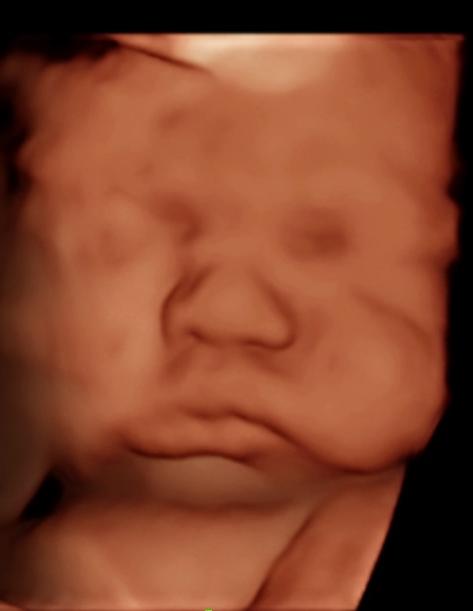

We are here to provide pregnancy confirmations; gender reveals and the most unforgettable 3D/4D experience for expectant mothers, in our cozy studio.

Seeing your baby is such a magical moment.